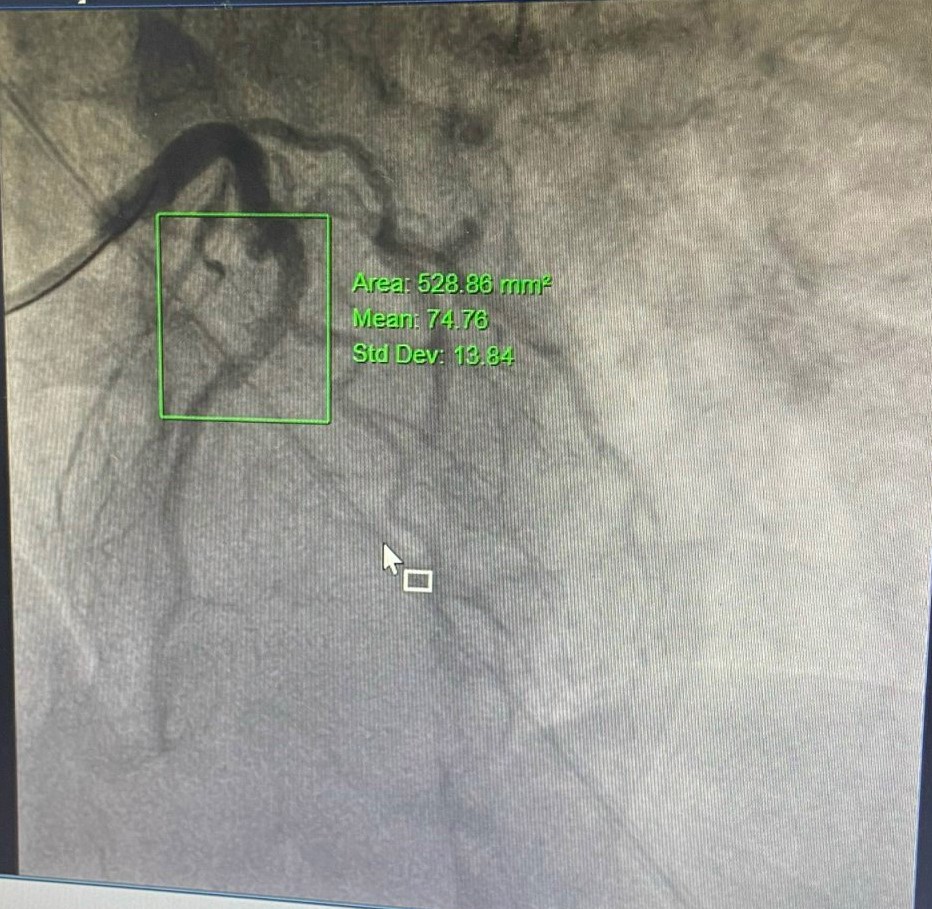

Kết quả chụp mạch vành cho thấy, hẹp 99% động mạch liên thất trước LAD I-II. Ngay lập tức, bệnh nhân được kíp Ths.BSNT Vũ Học Huấn – Trưởng Khoa Tim mạch – Đột quỵ, Ths.BS Phạm Văn Thuận cùng cộng sự thực hiện kỹ thuật can thiệp đặt 1stent mạch vành. Nhờ được phát hiện, can thiệp cấp cứu kịp thời mà bệnh nhân đã thoát khỏi giai đoạn nguy hiểm, đang dần phục hồi. Ghi nhận kỹ thuật đạt kết quả tốt.

Trường hợp thứ 2 trên bệnh nhân nam 80 tuổi, nửa tháng nay xuất hiện cơn đau thắt ngực không ổn định, tăng khi gắng sức, kéo dài 5-10 phút, khó thở trong cơn. Bệnh nhân có tiền sử COPD, giãn phế quản, tăng huyết áp, tiểu đường. Thực hiện chụp mạch vành qua da phát hiện bệnh nhân có tổn thương rất nặng, hẹp rất khít 2 thân động mạch vành; hẹp 99% liên thất trước (LAD) I-II, xơ vữa gây hẹp 99% động mạch mũ (LCx) I-II. Nếu không can thiệp kịp thời, bệnh nhân dễ dẫn đến nhồi máu cơ tim cấp và các biến chứng nguy hiểm. Bệnh nhân nhanh chóng được xử trí can thiệp, đặt 1 stent mạch vành tại vị trí LCx I-II. Sau can thiệp, bệnh nhân giảm cơn đau thắt ngực, nhánh thứ 2 sẽ can thiệp tiếp khi đã ổn định.